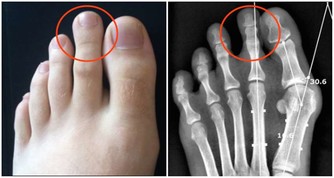

在放屁時不應出現不適感,氣味雖然難聞但不會極端惡臭。如果發現自己在排氣時,明顯感到腹痛,或是氣味比較異常,那麼應當立即去醫院進行相應檢查,食物不耐受和結腸癌等疾病都會引起這類病症。